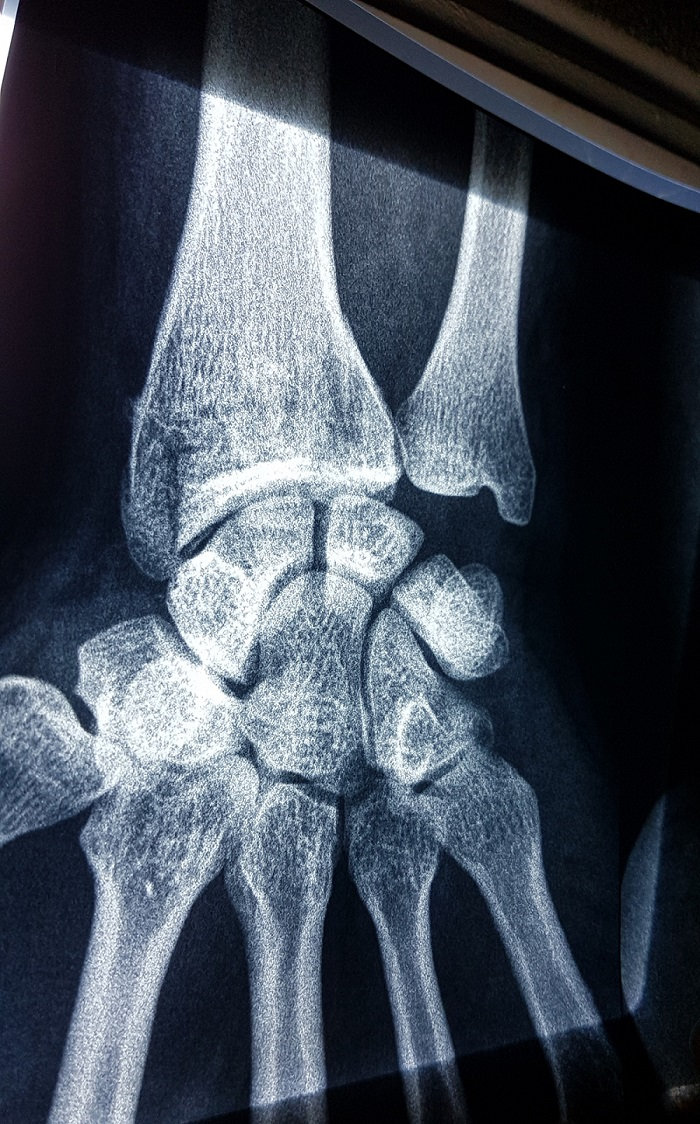

Le patient est un homme de 40 ans, il a fait une mauvaise réception (mal tombé) lors d'un coup de ciseaux au foot ...

Est ce qu'une attelle en plâtre jusqu'à la moitie de l'avant bras (pendant 21 jours) serait suffisante ?

qu'il remet tout en place ses os, et puis une attelle "élastoplast" pour une durée d'un mois, et si y a gonflement ben un an de galère...